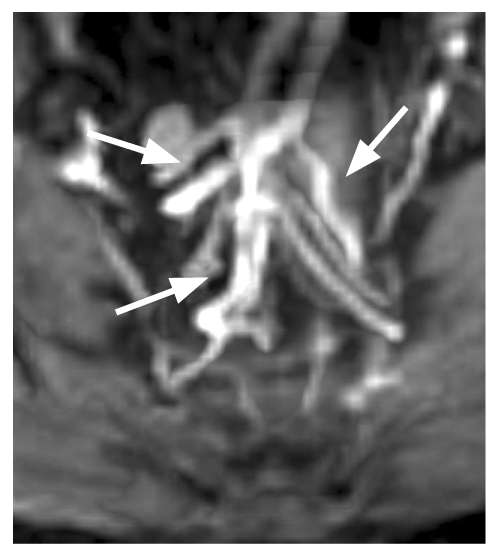

Рис. 4. Три ветви верхней прямокишечной артерии в момент отхождения (стрелки). Классический (1-й тип) анатомии верхней прямокишечной артерии.

Рис. 5. Три ветви верхней прямокишечной артерии до бифуркации (стрелки). Классический (1-й тип) анатомии верхней прямокишечной артерии.